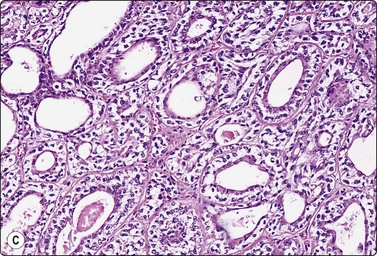

image image

Fig. 4.48 Acinic cell carcinoma

Epithelial fragments composed of cells with abundant vacuolated cytoplasm and relatively bland nuclei, resembling normal acinar cells; many naked nuclei; scanty, thin fibrovascular stroma. Note absence of well-formed acinar structures (A, MGG, IP; B, Pap, HP).

Criteria for diagnosis

Abundant cell material with a clean background,

Cells mainly in clusters, scanty inconspicuous fibrovascular stroma,

Microacinar groupings,

Abundant, fragile, finely vacuolated, occasionally dense oncocyte-like cytoplasm,

Rounded, medium-sized nuclei, mild to moderate anisokaryosis, bland chromatin,

Many stripped nuclei.